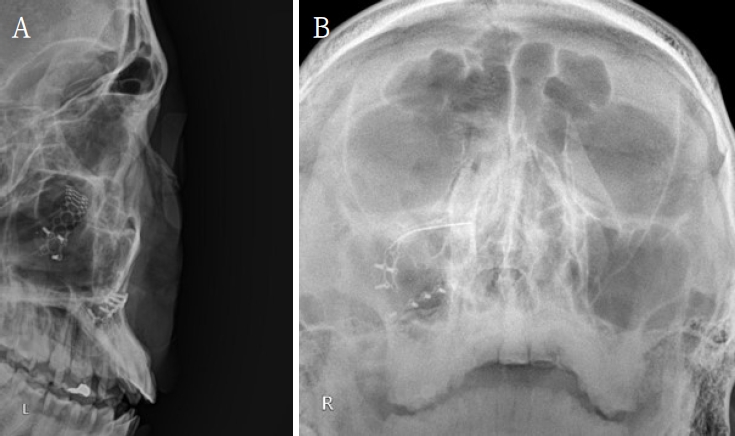

Postoperative radiographs show stable fixation and orbital symmetry. A. Lateral skull radiograph shows intact titanium miniplate fixation of the left orbital floor without displacement. B. Waters’ radiograph demonstrates symmetric orbital outline and stable reconstruction compared with the contralateral side.